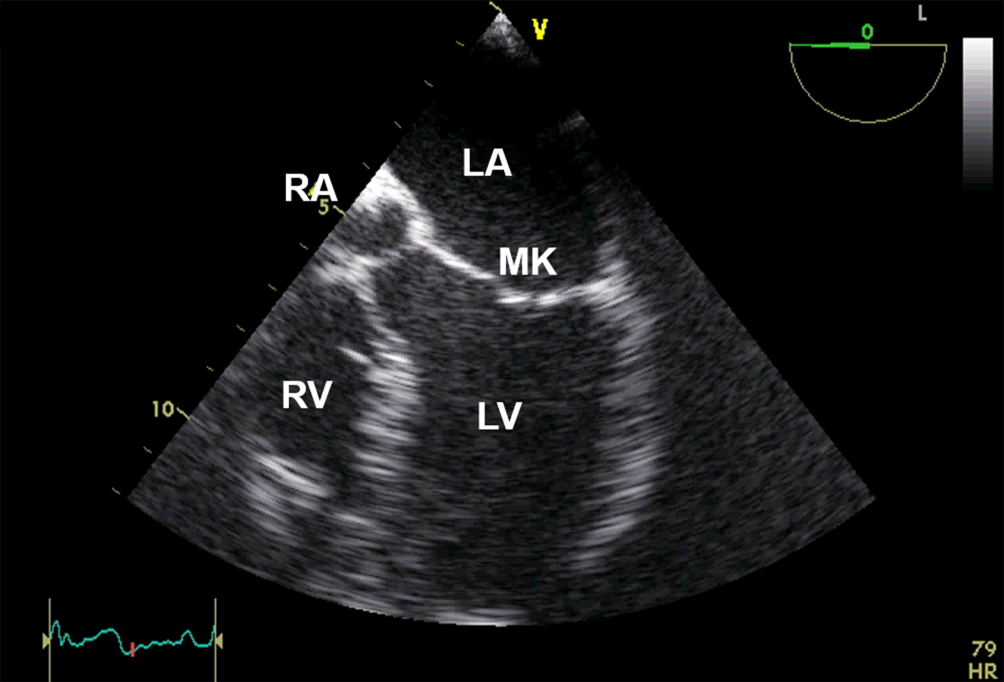

Anlotebene: 4‑Kammer-Blick

Sondenposition: mittösophageal

Rotationswinkel: 0°